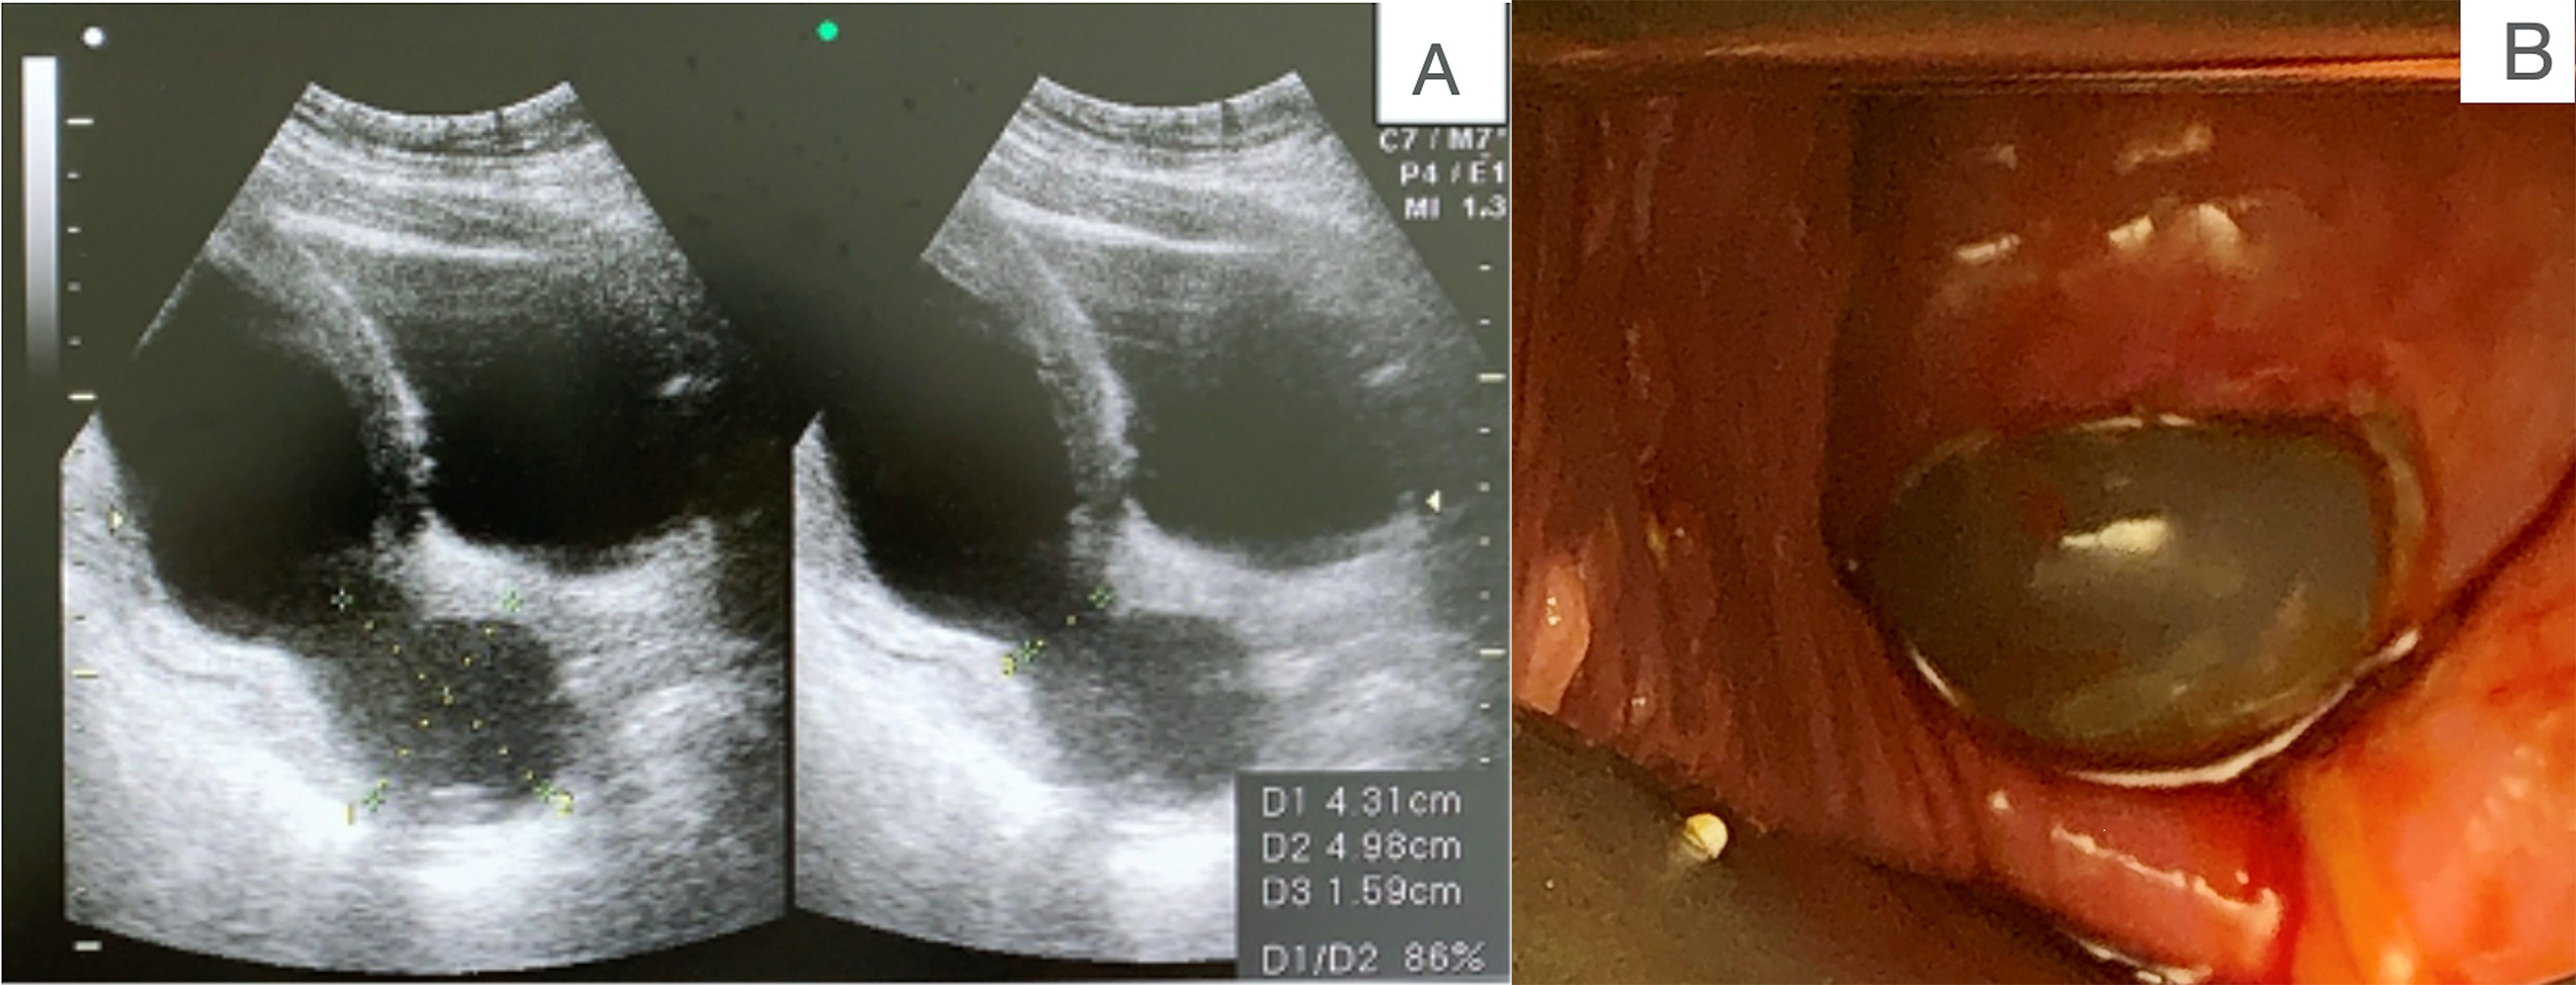

At admission, the patients underwent history taking, laboratory studies, fetal sonography (Fig. 1A), speculum examination (Fig. 1B), and tocodynamometry. Cervical cultures were collected in the lower genital tract. Rescue cerclage was performed under epidural anesthesia. Pre-operatively, prophylactic antibiotics were given, the bladder was emptied, and the vulva and vagina were sterilized with betadine solution, and then rinsed quickly with sterile saline to avoid irritation to the fragile amniotic membranes. In the Trendelenburg position, the operation started by reducing the protruding amniotic bag slowly and carefully with a large rinsed cotton swab until the effaced cervix could be visualized. A 16-French foley catheter was inserted into the uterine cavity with a balloon and gradually inflated while retrieving the cotton swab. The cervix was then grasped with Allis forceps at 0, 3, 6 and 9 o’clock positions. The McDonald suture was performed with one or two Mersilene tapes at the operator’s discretion (Fig. 2). The intrauterine Foley catheter was carefully deflated and removed while tying the tape(s).

Fig. 1.Diagnosis of cervical insufficiency. (A) Transabdominal sonography finding of a prolapsed amniotic sac. (B) Speculum examination of cervical insufficiency.